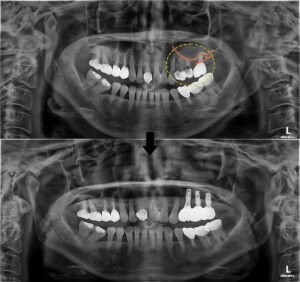

반대쪽과 비교해 보시면

상악동 거상술을 진행한 부위가 하얗게

뼈로 찬 모습을 보실 수 있는데요.

임플란트가 식립될 공간이 충분히 확보되어

다행히 부작용 없이 안정적으로

식립되었어요.👏👏

전, 후 사진을 보시면 확실히 비교가 되실텐데요❗

환자분께서는 생각보다 짧았던 수술 시간과

마치 자연치아처럼 자연스러운 모습에

매우 만족해 하셨답니다.😀